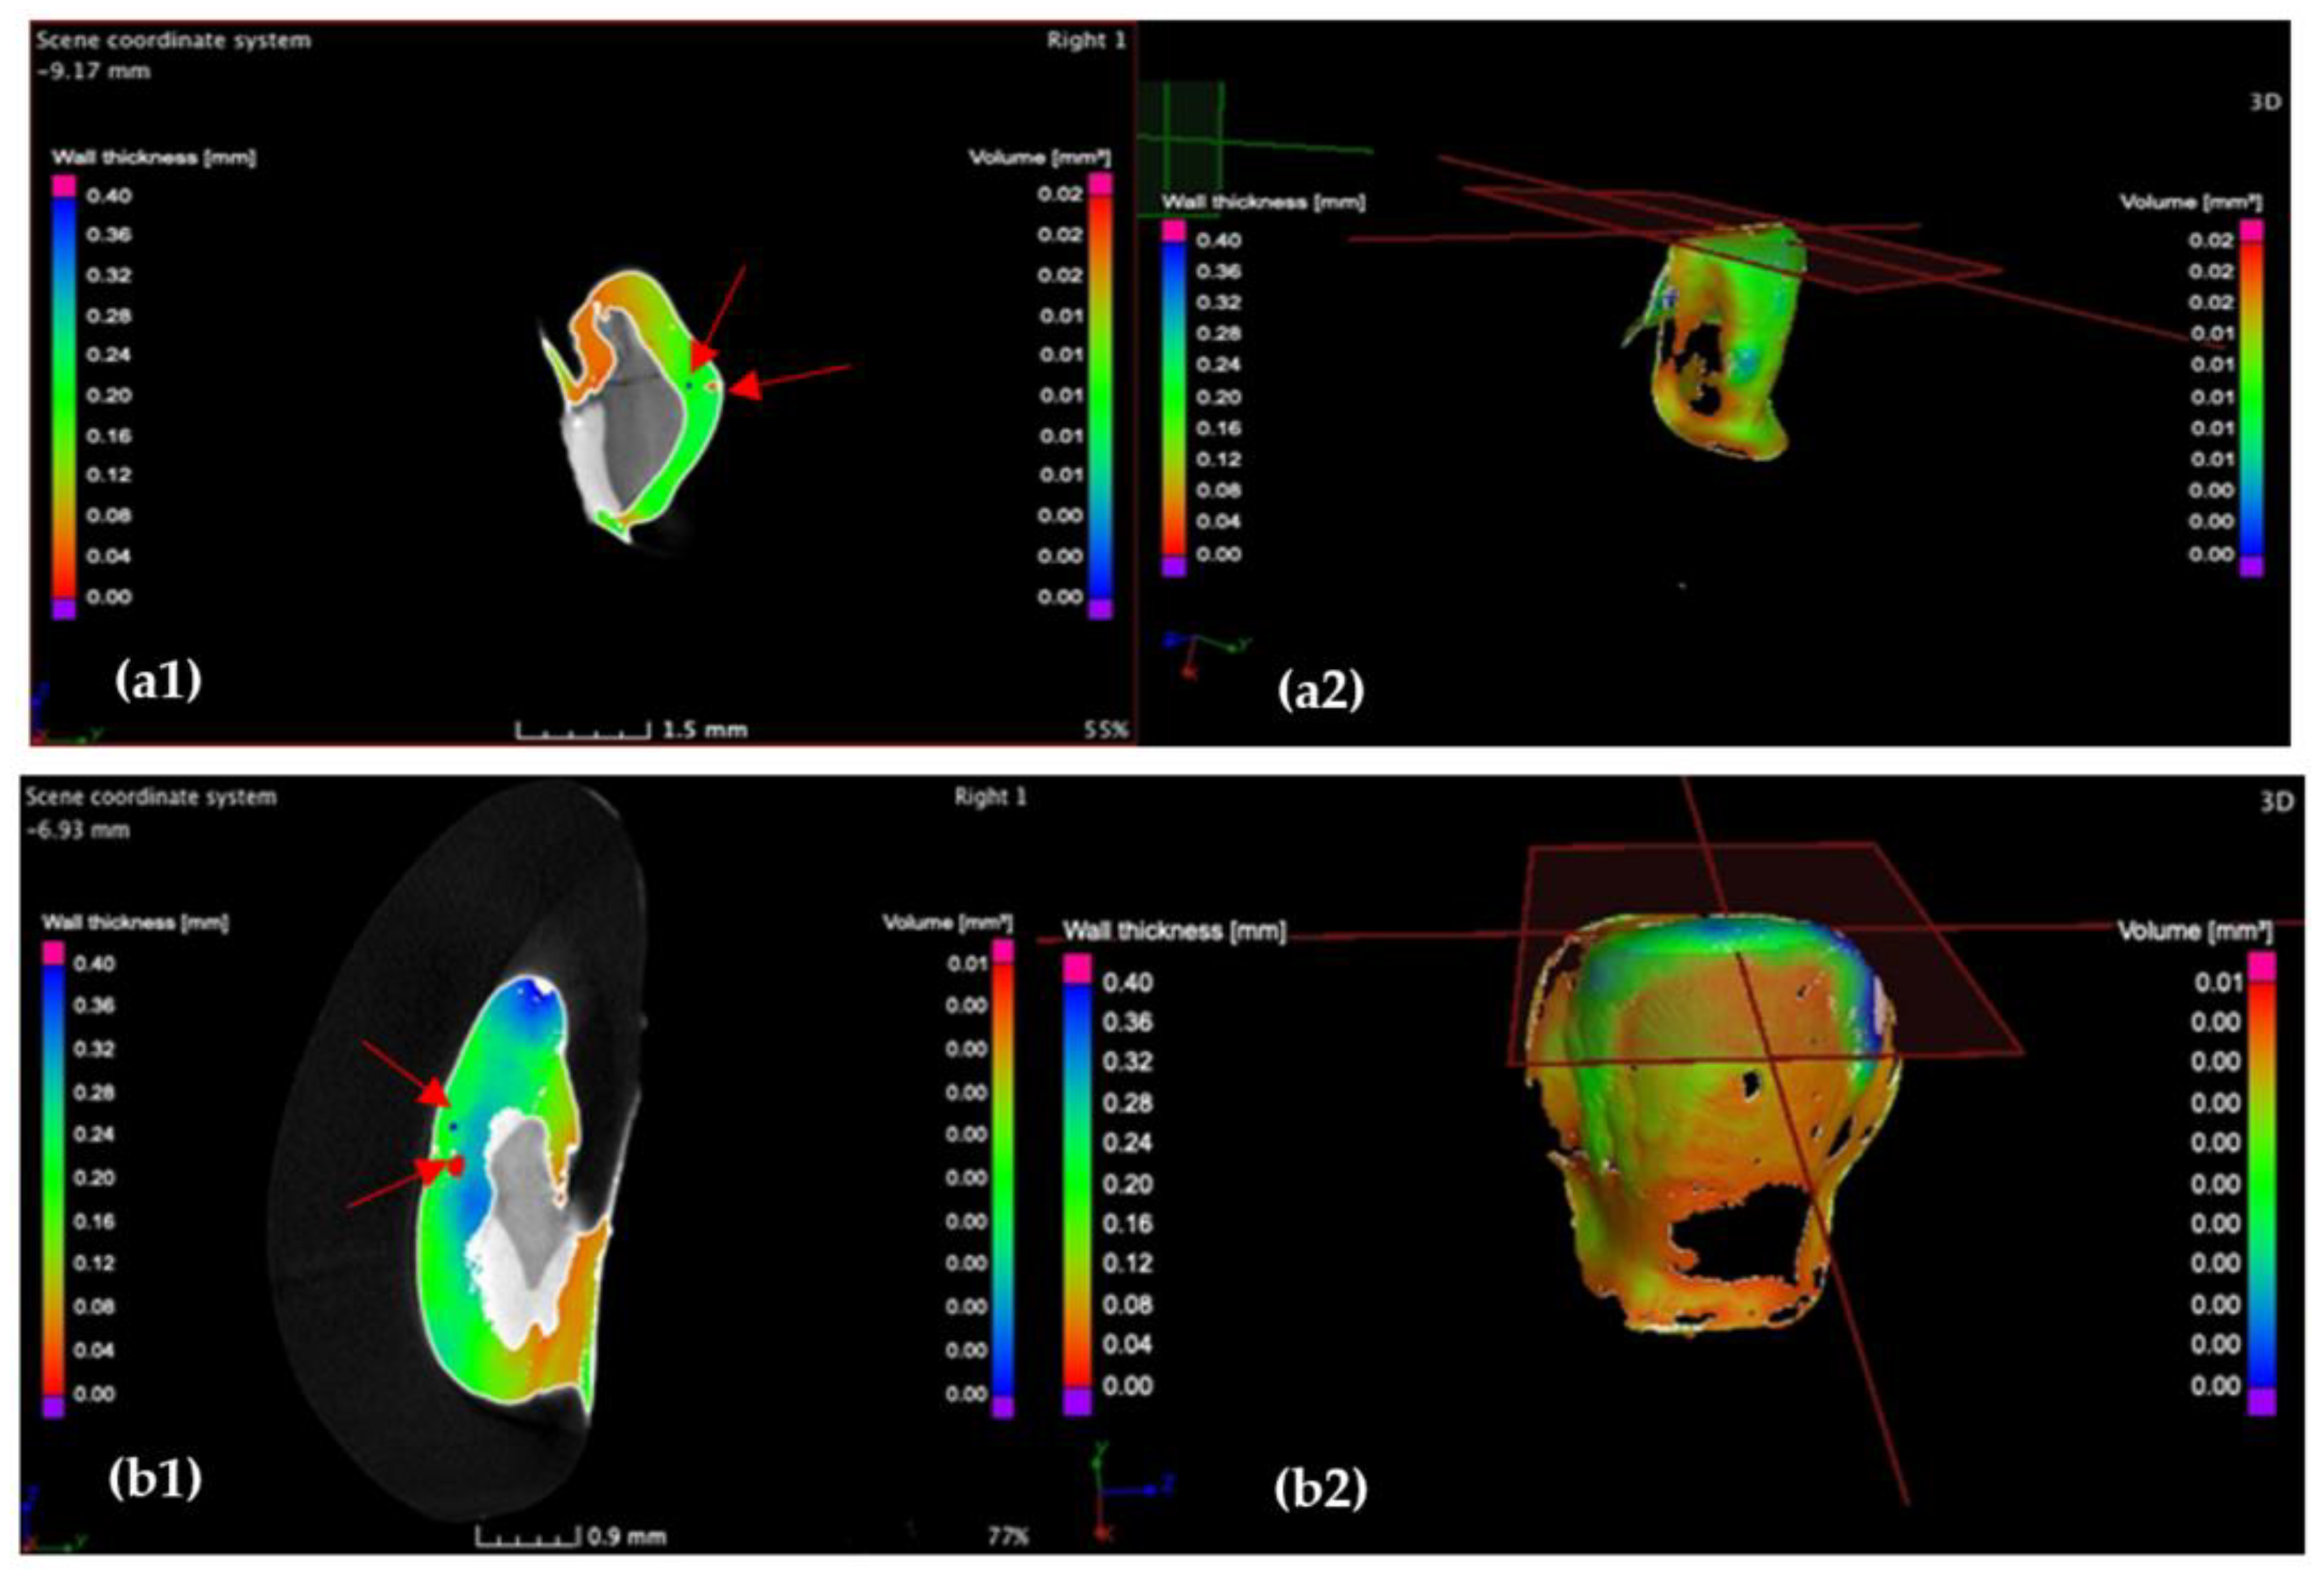

3.2. Micro-CT

3.4. Porosity Results